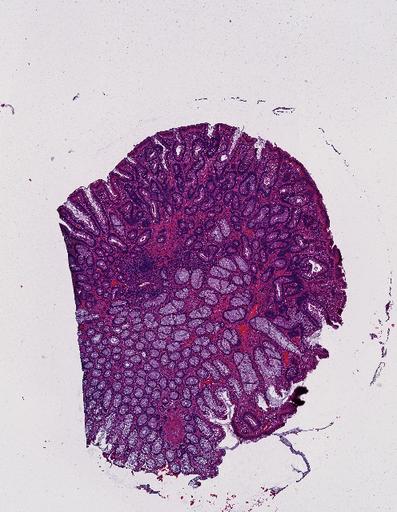

High‑resolution three‑dimensional (3D) tissue atlases promise to redefine how we study cellular architecture‑function relationships in human tissues. Large-scale consortia such as the Human Bimolecular Atlas Program (HuBMAP) systematically build detailed 3D organ maps by profiling serial tissue sections with single-cell spatial technologies. However, an accurate and efficient reconstruction method that can handle atlas-scale datasets remains elusive. We introduce Space-map, an open-source method that integrates single‑cell coordinates with optional histological image features to assemble serial sections into 3D models. Space‑map combines multi‑scale feature matching with large‑deformation diffeomorphic metric mapping, delivering global reconstructions while preserving local micro‑anatomy. To demonstrate the capability of Space-map, we generated a serially sectioned spatial transcriptomics (Xenium, ~2.9M cells) dataset and a spatial proteomics dataset (CODEX, ~2.4M cells). Applying Space-map to these single-cell spatial maps, we built three 3D models for both diseased (colon polyp) and reference colon tissues. These high-resolution 3D models showcase the intricate structure of the human colon across different states. Space-map is fast and highly efficient. We demonstrated its performance and accuracy using in‑house and public datasets. The result shows that Space‑map is 10 times faster and ~2‑fold more accurate than PASTE and STalign, making 3D atlas reconstruction more accessible. Our study provides a new robust and user-friendly software available at https://github.com/a12910/spacemap that can be easily applied for constructing molecular 3D tissue maps of human organs at single-cell resolution.